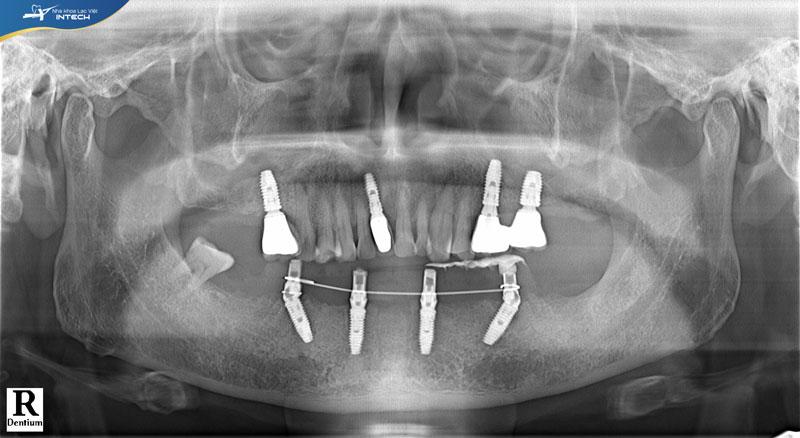

Dưới đây là hình ảnh phim chụp X-quang của chú Nguyễn Trà Lý sau khi cấy ghép Implant:

Hình ảnh phim CT của chú Lý sau khi cấy ghép Implant All On 4 toàn hàm dướiHình ảnh phim CT của chú Lý sau khi cấy ghép Implant All On 4 toàn hàm dưới